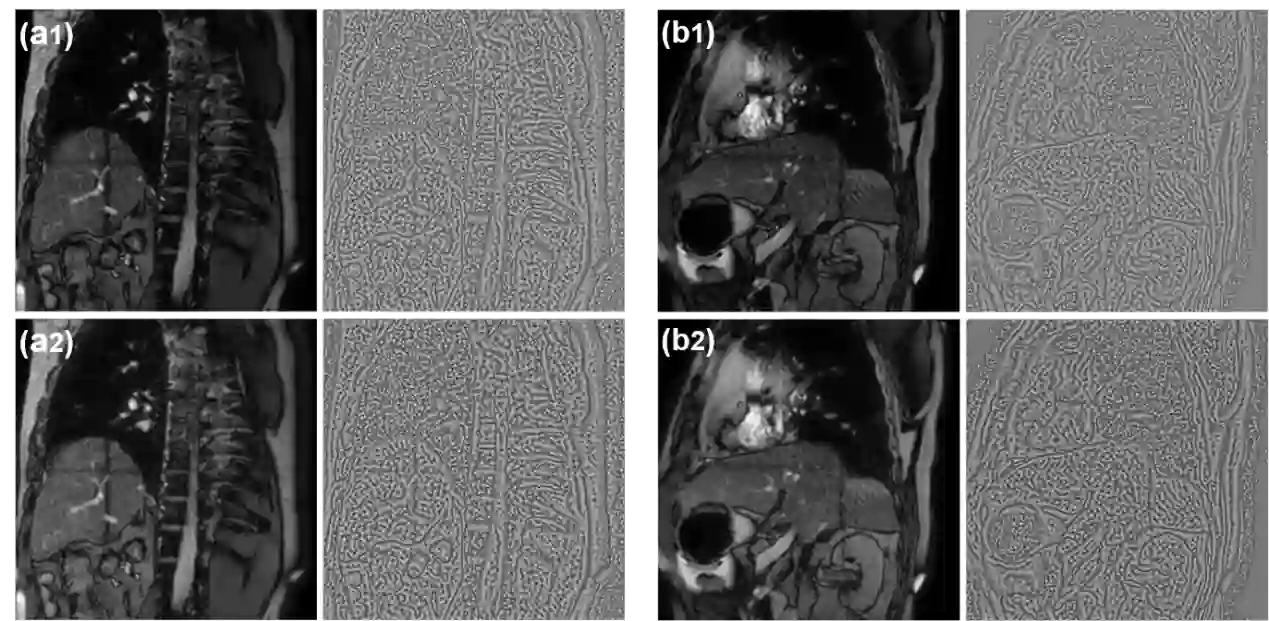

Objective:To develop a no-reference image quality assessment method using automated distortion recognition to boost MRI-guided radiotherapy precision.Methods:We analyzed 106,000 MR images from 10 patients with liver metastasis,captured with the Elekta Unity MR-LINAC.Our No-Reference Quality Assessment Model includes:1)image preprocessing to enhance visibility of key diagnostic features;2)feature extraction and directional analysis using MSCN coefficients across four directions to capture textural attributes and gradients,vital for identifying image features and potential distortions;3)integrative Quality Index(QI)calculation,which integrates features via AGGD parameter estimation and K-means clustering.The QI,based on a weighted MAD computation of directional scores,provides a comprehensive image quality measure,robust against outliers.LOO-CV assessed model generalizability and performance.Tumor tracking algorithm performance was compared with and without preprocessing to verify tracking accuracy enhancements.Results:Preprocessing significantly improved image quality,with the QI showing substantial positive changes and surpassing other metrics.After normalization,the QI's average value was 79.6 times higher than CNR,indicating improved image definition and contrast.It also showed higher sensitivity in detail recognition with average values 6.5 times and 1.7 times higher than Tenengrad gradient and entropy.The tumor tracking algorithm confirmed significant tracking accuracy improvements with preprocessed images,validating preprocessing effectiveness.Conclusions:This study introduces a novel no-reference image quality evaluation method based on automated distortion recognition,offering a new quality control tool for MRIgRT tumor tracking.It enhances clinical application accuracy and facilitates medical image quality assessment standardization, with significant clinical and research value.